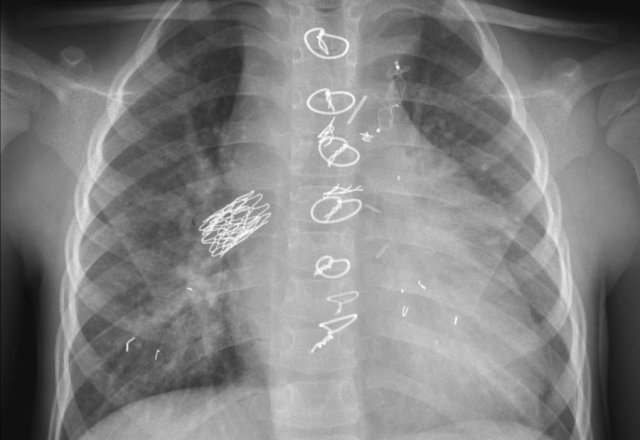

First study the images.

Then continue reading.

The findings are:

• Two epicardial leads connected to pacemaker

• ICD

• two leads to right ventricular apex

• one lead contains two shock coils

• tricuspid valve (arrows)

• mitral valve